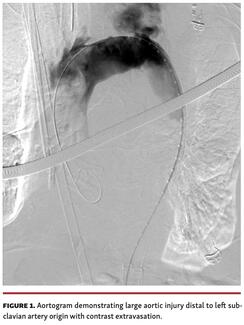

This case demonstrates a rare but catastrophic complication of transcatheter aortic valve replacement (TAVR). In an era where TAVR is now indicated in low-risk patients, serious complication rates are less frequent. It exemplifies the...